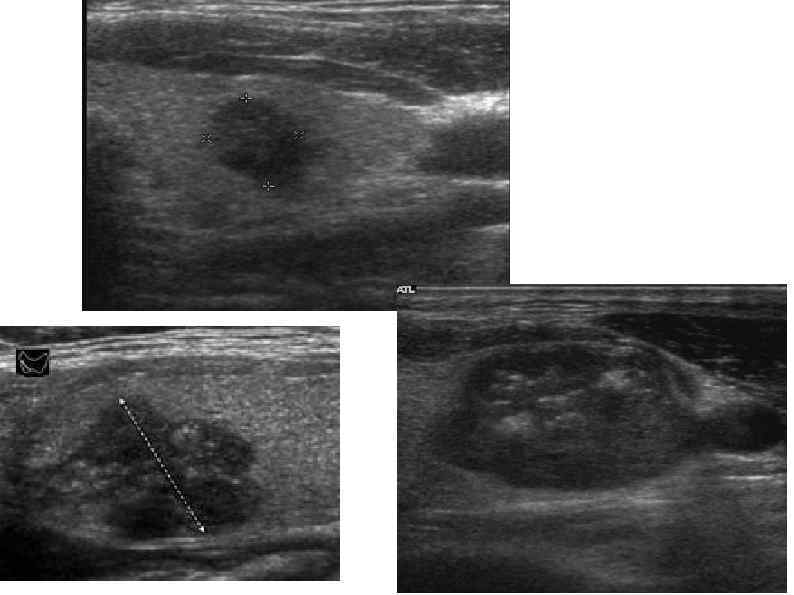

Ультразвуковое исследование. Можно выявить узлы ЩЖ диаметром от 3 мм и заполненных жидкостью кист Ультразвуковое исследование. Можно выявить узлы ЩЖ диаметром от 3 мм и заполненных жидкостью кист от 2 мм. Возможно опеределить степень васкуляризации( доплер). Определить размер, обьем и характеристику ткани ЩЖ. Выявление езлов: количество, диаметр, форма, эхогенность, границы, наличае кальцификатов. Выявление лимфатических узлов. Генри М. Кроненберг, Шломо Мелмед, Кеннет С. Полонски, П. Рид Ларсен ЭНДОКРИНОЛОГИЯ ПО ВИЛЬЯИСУ. Заболевания щитовидной железы. 2010 г. (стр. 299)

Признаки потенциально злокачественного узла Солидный, гипоэхогенный. Размер узла более 1 см Неровные контуры. Микрокальцинаты. Признаки потенциально злокачественного узла Солидный, гипоэхогенный. Размер узла более 1 см Неровные контуры. Микрокальцинаты. Хаотичная или повышенная васкуляризация Толщина больше ширины Рост за пределы капсулы ЩЖ Наличае 2 и более признаков резко повышает вероятность рака!